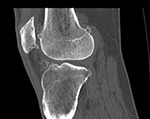

Your knee will be included in the CT scan to further improve alignment.

The CT scan allows us to create the patient-specific parameters used to plan and perform your surgical procedure with enhanced accuracy.